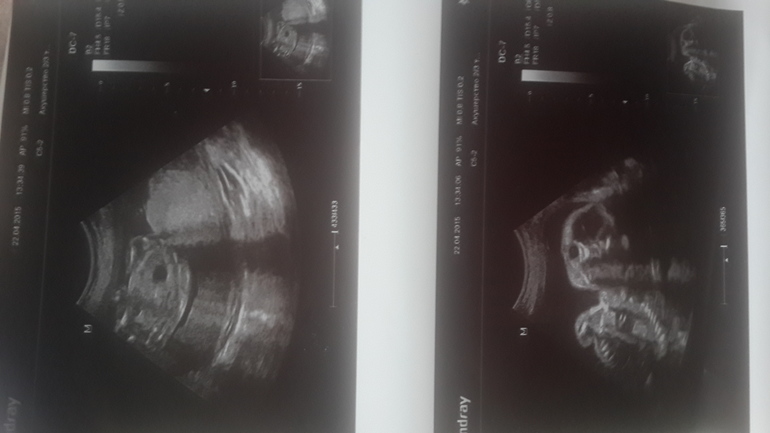

Повторное УЗИ.

Диагноз маленькой девочки подтвердился. Рекомендуют рожать там где есть перенат. центр в Балашихе. Маленькую после родов сразу надо оперировать, т. к.желудок находится в области сердца.